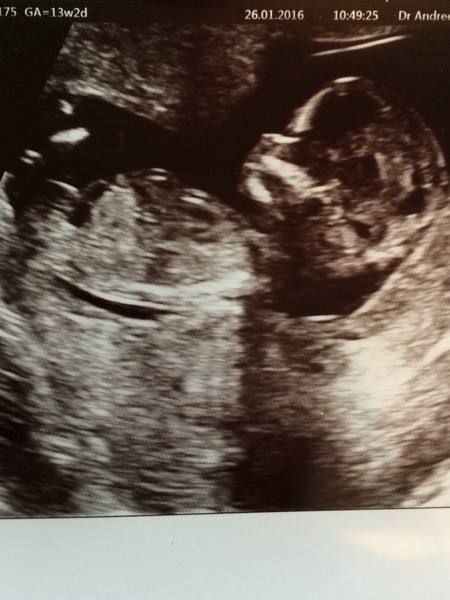

Sophia1984 · 26/01/2016 18:45

Hi everyone. Exciting day here as we got to see little baby doing somersaults and 'waving' at the camera! Baby is measuring 12w5d so 4 days ahead of LMP date (my instinct was right!) Midwife was so, so lovely and it was absolutely amazing to see little one appear straight away and hear and see the heartbeat when I was expecting bad news. Thank you for all your support so far Grin

Scan was lovely this evening. Sonographer took lots of time to show us all everything. All looking good.

Congrats on your scans Sophia and Elle! Elle those pictures are just amazing, those little feet, wow!